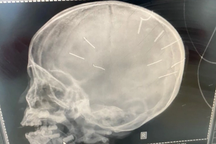

Trong phiên tòa xét xử bị cáo Nguyễn Trung Huyên (30 tuổi, ở xã Thạch Hòa, huyện Thạch Thất, Hà Nội) về các tội "Giết người" và "Cố ý gây thương tích", trong vụ án bé gái Đ.N.A. (SN 2018) bị hành hạ, đóng 10 đinh vào đầu gây tử vong, kiểm sát viên và các luật sư đặt nhiều câu hỏi liên quan đến vai trò của người mẹ là chị Nguyễn Thị Luyến.

Ông Hiển trình bày trước HĐXX về việc vào đêm 17/1, khi cháu N.A. được đưa vào viện cấp cứu với 10 chiếc đinh trong đầu, chị Luyến đã nhắn tin cho Huyên: "Dù có chuyện gì xảy ra, em vẫn yêu anh, em không thể sống thiếu anh". Luật sư Hiển đặt nghi vấn rằng Luyến biết những hành động Huyên làm với con gái nhưng vì tình yêu cho bị cáo mà Luyến "nhắm mắt cho qua".